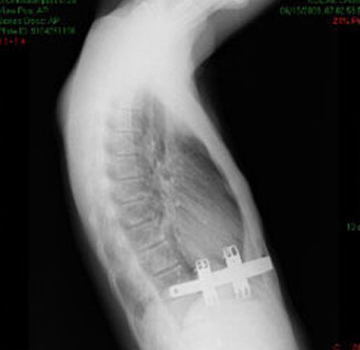

Pektus Arkuatum

Pektus Arkuatum (Mikst Deformite)

Pektus ekskavatum sternum ve kıkırdak kostaların değişik derecelerde depresyonu ile karakterize ...